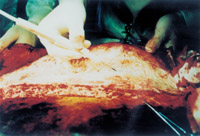

3-4 用電手術(shù)刀從尚未被燒傷的皮下組織下層、深筋膜上將燒傷皮膚及皮下組織一起切除

3-5 這是皮膚及皮下組織被切除后的創(chuàng)面情況,表現(xiàn)為深筋膜存在的肌肉層創(chuàng)面

3-6 處理結(jié)果:燒傷皮膚及未燒傷的皮下組織均被切除,胸部燒傷創(chuàng)面變成人為的外科手術(shù)切除的肌肉層創(chuàng)傷創(chuàng)面,已無任何燒傷組織及皮膚組織。